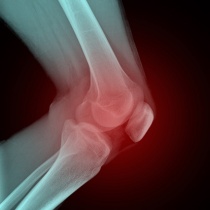

La première complication de l’arthrose est l’intensification de la douleur. Elle peut, dans certains cas, devenir insupportable et se manifester la nuit et/ou lorsque l’articulation est au repos. Cette évolution montre qu’une inflammation est venue s’ajouter au phénomène d’usure.

Les déformations peuvent elles aussi s’accentuer.

La raideur peut se prolonger plus longtemps qu’au début et la difficulté de marcher peut s’amplifier jusqu’à ce que la personne atteinte n’y parvienne plus du tout.